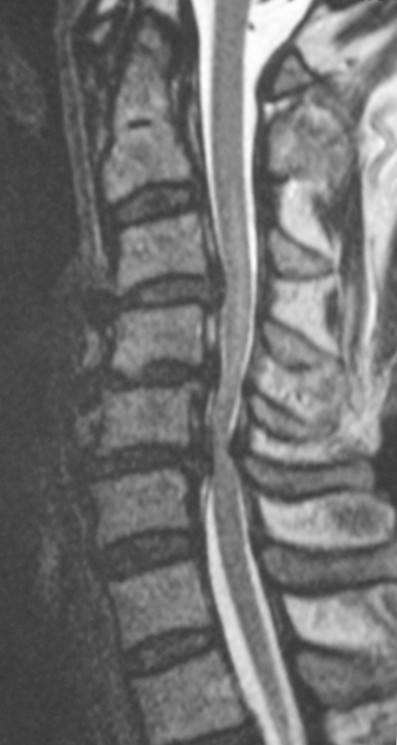

这名患者颈椎管狭窄,造成双手及双脚痲痹无力。

其中一名双脚无力的病人晚上不小心向前摔倒后,双手亦变得无力。他的医生帮他加做了颈椎扫描,这才发现原来他的脊髓神经受压。

脊髓神经是脑部的延续,由颈椎延伸到上腰椎,可以说是脑部向身体各个部位发出命令和接收讯息的总电缆。神经线由左脑和右脑伸延出来之后经过脑干就集中在脊椎的椎管内。如果因为椎间盘突出、增生或其他原因而造成脊髓神经受压,大多数患者会左右两边身体同时受到影响,例如双手痲痹迟钝,双脚僵硬无力,行走不稳。